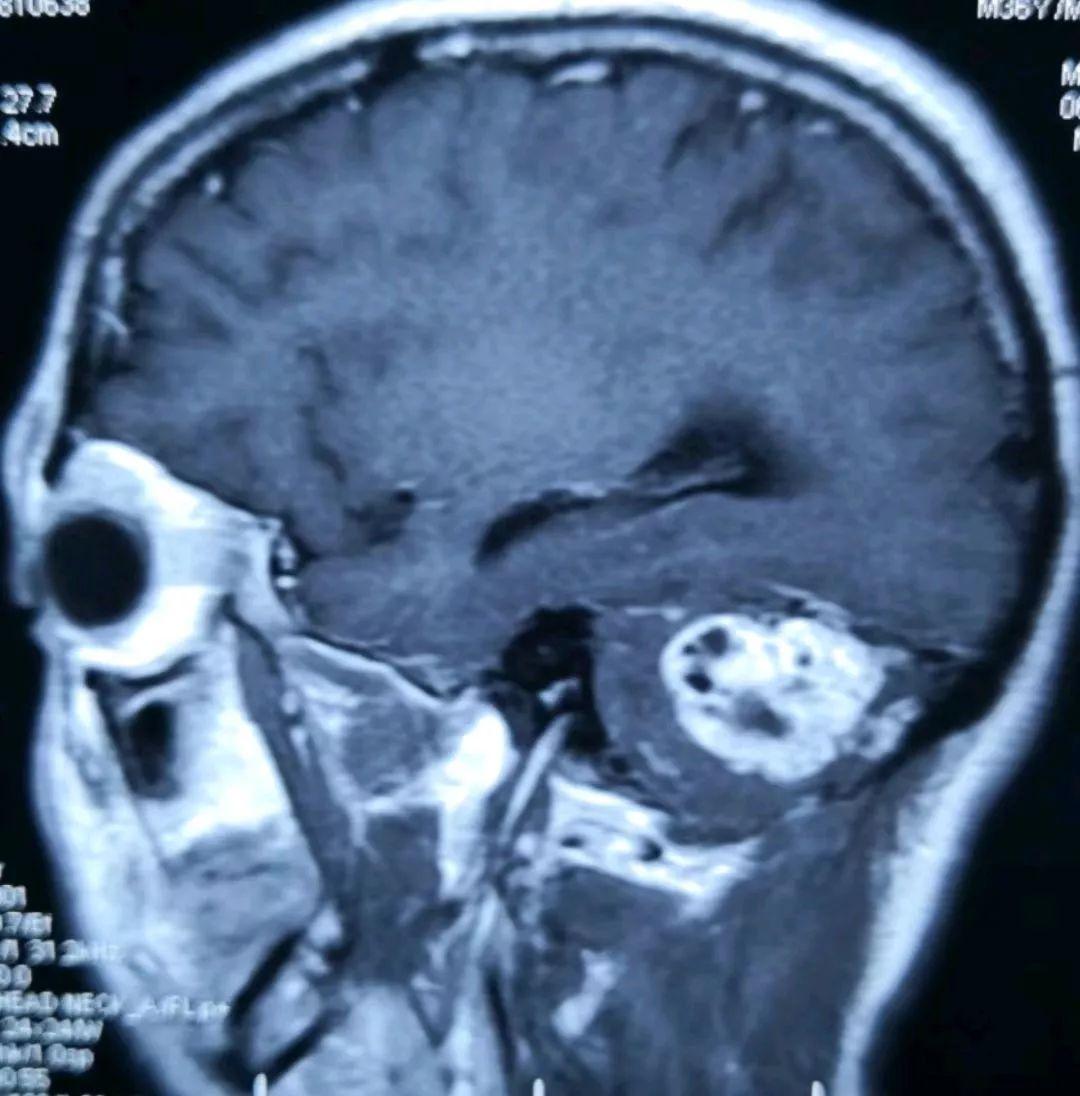

术前的磁共振片子提示右侧小脑半球的实质性血管母细胞瘤,增强显著(提示血供丰富)